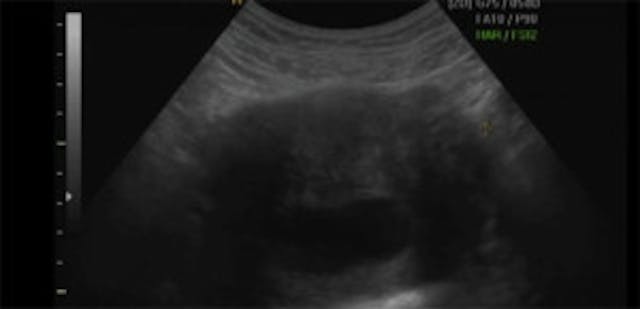

Sonogram of Knowles’ daughter Blue Ivy.